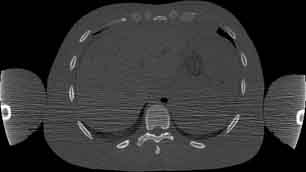

Visible Human male: Sectio transversalis 1509

CT